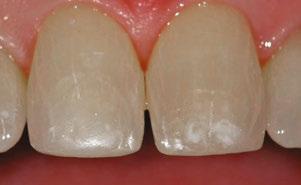

Case 2

A 3-year-old female presented with pulpal necrosis and abscess on #E and pulpal necrosis on #F. Extraction therapy or pulpectomy was offered. The family was highly motivated to retain #E and #F. The pulpectomy was performed with 0.02 K-Flex hand files, 3% NaOCl with a lateral vented needle, obturated with Vitapex (Neo Dental International Inc., Federal Way, Washington), a premixed paste of calcium hydroxide and iodoform. The access was filled with a HVGIC sealing the pulp therapy and increasing the clinical success by minimizing the potential for bacterial contamination. NuSmile ZR anterior crowns were selected as offering a full-coverage, esthetic, cemented restoration with no polymerization shrinkage when compared to a composite restoration. Crowns were cemented with NuSmile® BioCem (NuSmile, Houston, Texas). This is clinically beneficial as the provider would want to cement a restoration that provides limited microleakage minimizing the potential for bacterial contamination.15-17 At 6-month follow up, lesion healing had occurred with healthy gingival margins and no plaque accumulations (Figure 3).

Figure 3: NuSmile® ZR Crowns were selected as a cementable full coverage restoration. At 6-month recall, apical tissues were healed with excellent gingival health Figure 4: SMART style restorations that were definitively restored with NuSmile® ZR Crowns as an esthetic option to cover SDF staining